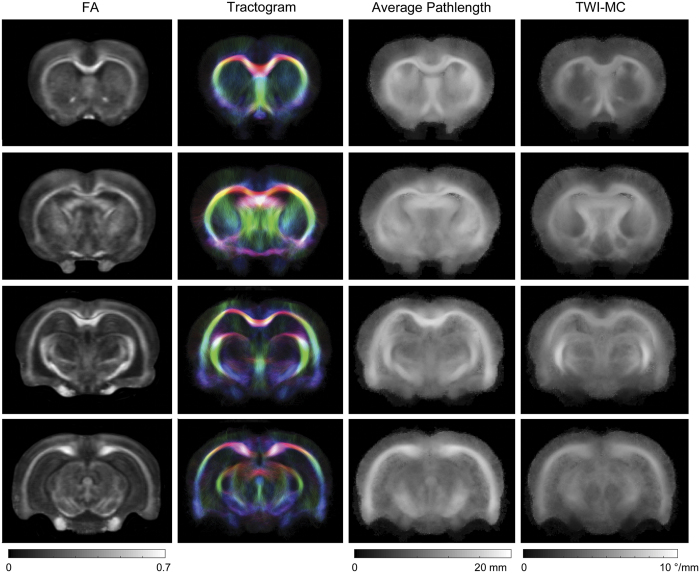

Tractograms were registered to the final DTI template using the DTI-to-template diffeomorphisms ensuring that both the length and spatial location of the streamlines were normalized36. The tractograms were then used to generate two tract-weighted images: average pathlength map, representing the average length of tracks passing through each voxel36; and track-weighted curvature map, representing the average curvature of all tracks passing through each voxel (TWI-MC). Tractogram derived average pathlength and TWI-MC images show novel contrast not observed in diffusion tensor images such as FA (see Fig. 1). As with the tensor measures, the median of each was calculated for the a-priori ROIs.

Figure 1. Tract-weighted imaging provides additional contrast to traditional diffusion tensor imaging.

Example FA, tractogram, average pathlength and TWI-MC template images for sham rats at D30. Tractogram images were generated with one million streamlines, colour-encoded according to orientation: red, lateral/medial; green, superior/inferior; blue, anterior/posterior. Average pathlength and TWI-MC images calculated from the tractograms show novel contrast compared to the FA map. TWI-MC = track-weighted mean curvature.